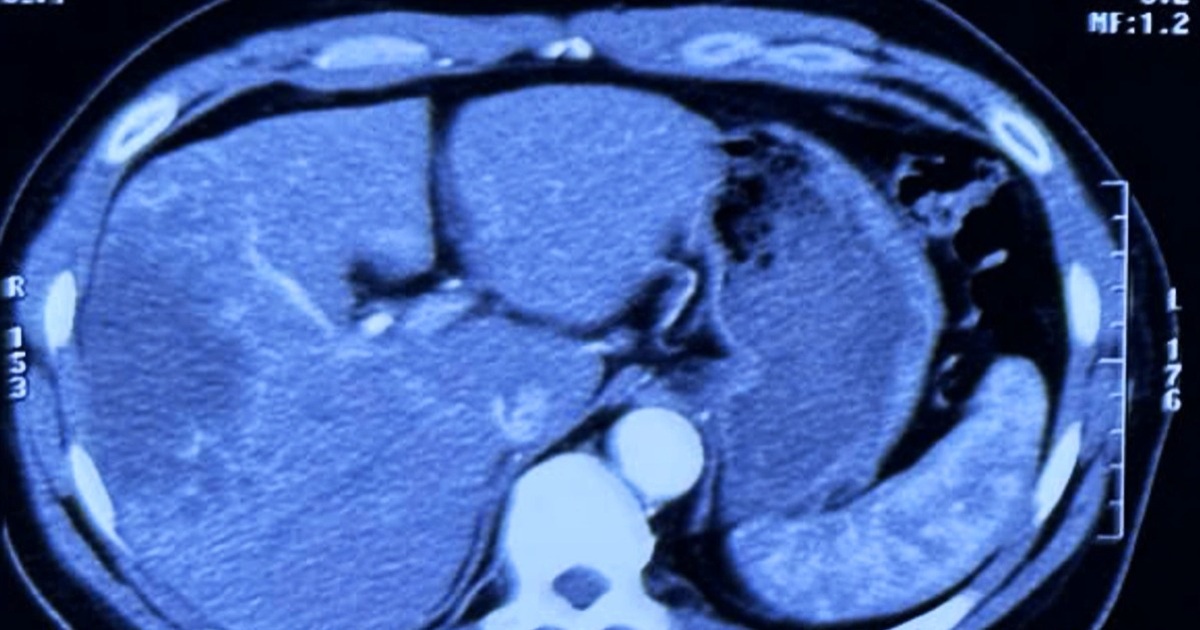

Căn bệnh ung thư 80% ca mắc phát hiện đã trễ, “tử thần” từ món gỏi cá sống

Tại Hội nghị khoa học Trung tâm Ung bướu Bệnh viện Chợ Rẫy 2025, diễn ra các ngày 2-3/10, BSCK2 Vương Đình Thy Hảo, Phó trưởng khoa Hóa Xạ trị, Trung tâm Ung Bướu đã có bài báo cáo về “Vai trò kéo dài sống còn của liệu pháp miễn dịch trong điều trị ung…